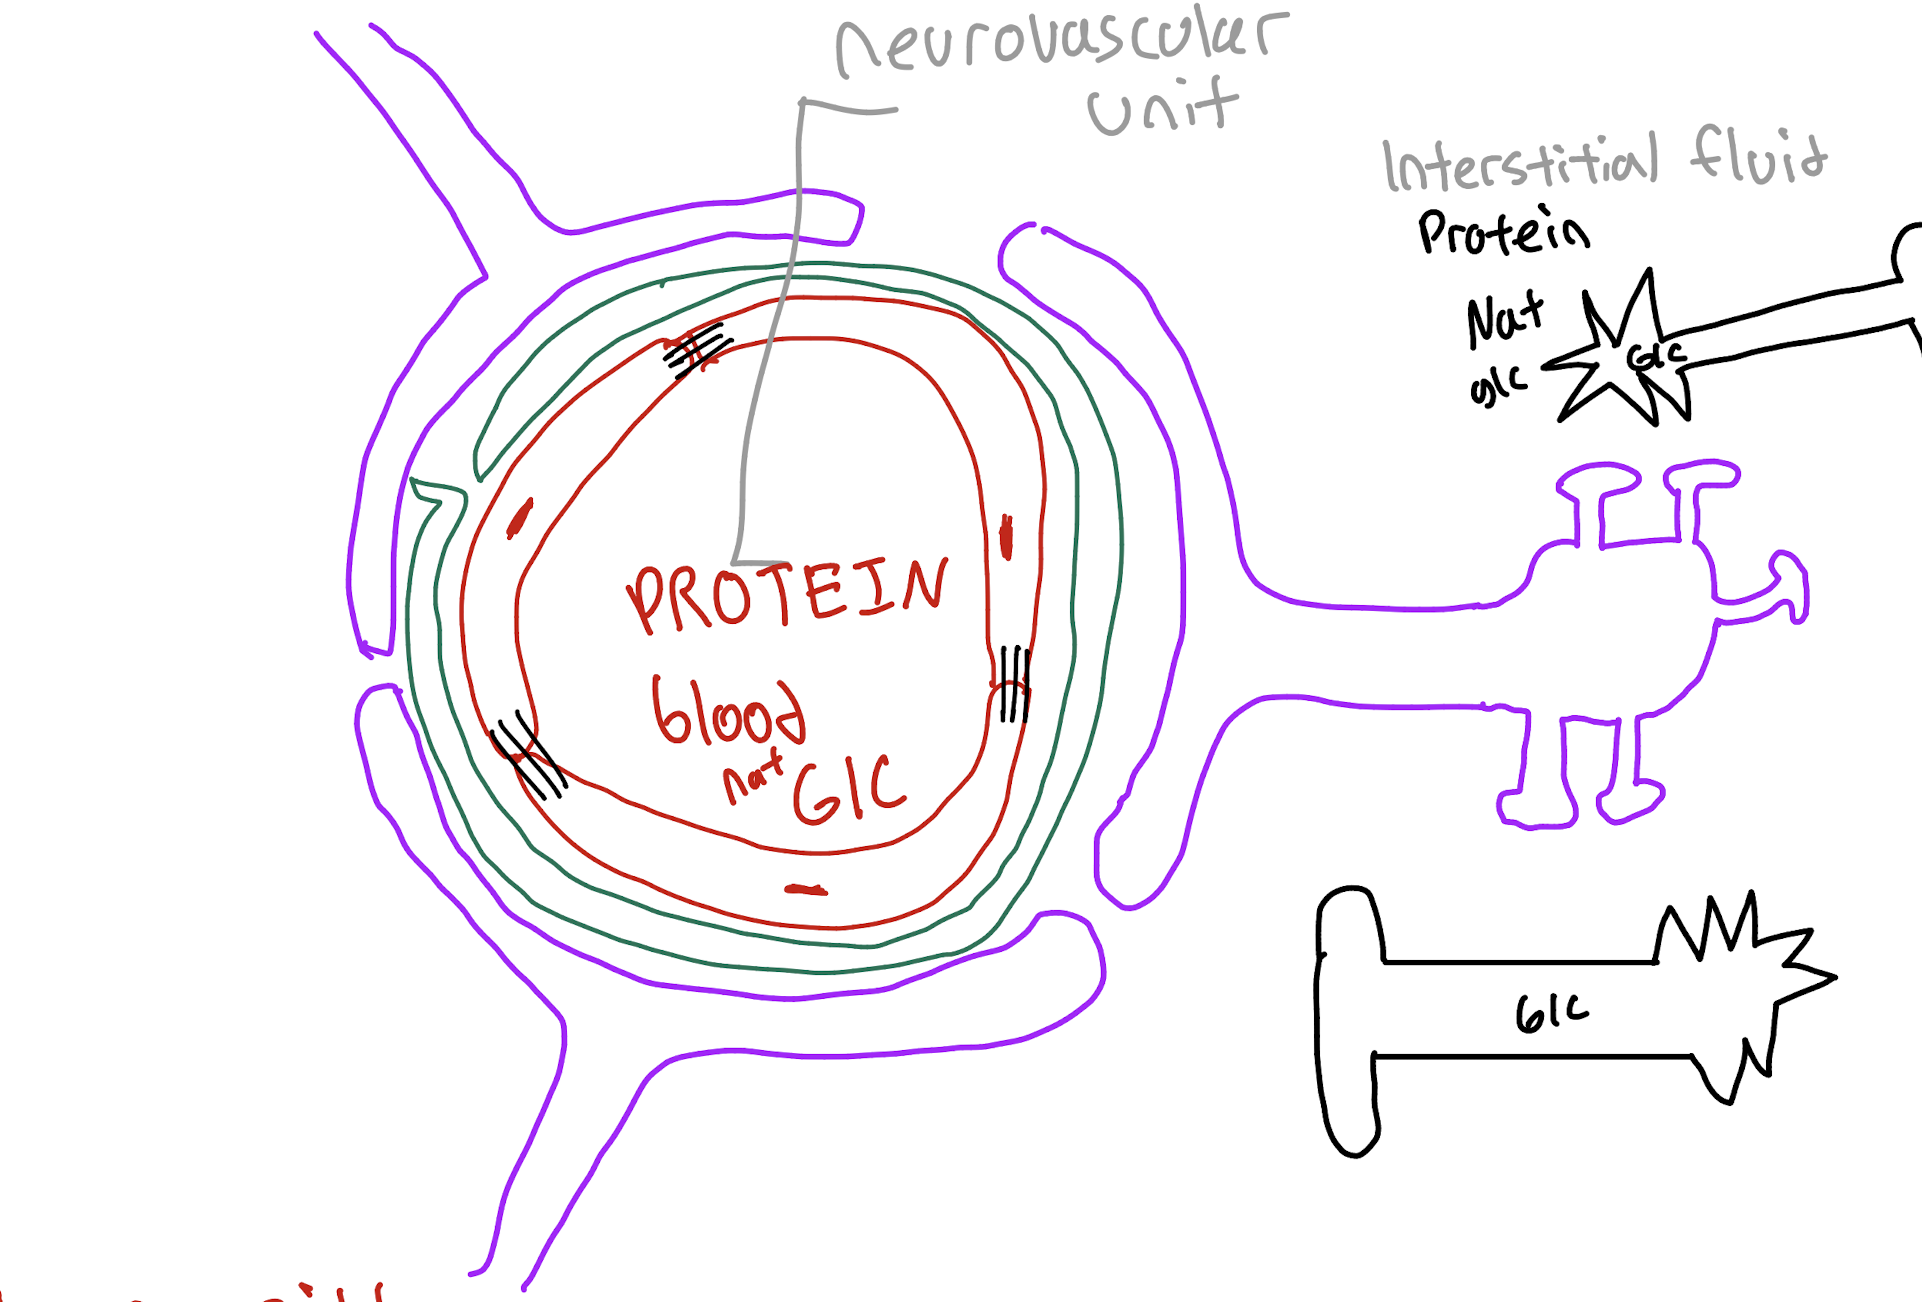

What Three cells/Structures make up the Neuromuscular unit (BBB)

(1) capillary endothelium

(2) pericyte

(3) astrocyte

What is the role of the capillary endothelium in the BBB

The main physical barrier that prevents protein,virus and bacteria from getting into the brain

What is the role of the pericyte in the BBB

Strengthens and controls vessel function (stabilizer)

What is the role of the Astrocyte in the BBB?

Does regulation of blood and supports it (Caretaker)

Why does the brain maintain a low-protein environment?

To limit cell proliferation (stop cell growth and spreading)

What is the primary source of energy for the brain?

Glucose (consumes about half of the body's glucose)